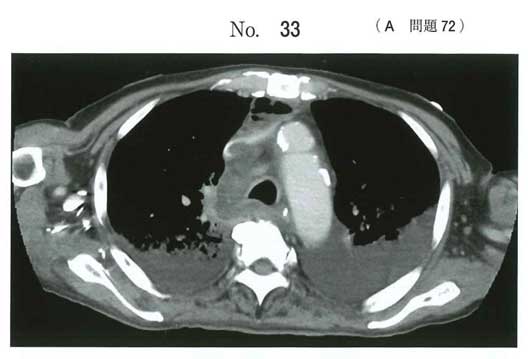

降下性壊死性縦隔炎、aeが正解

頸部から下降する痛み、炎症反応がヒントですが画像だけでは厳しい…